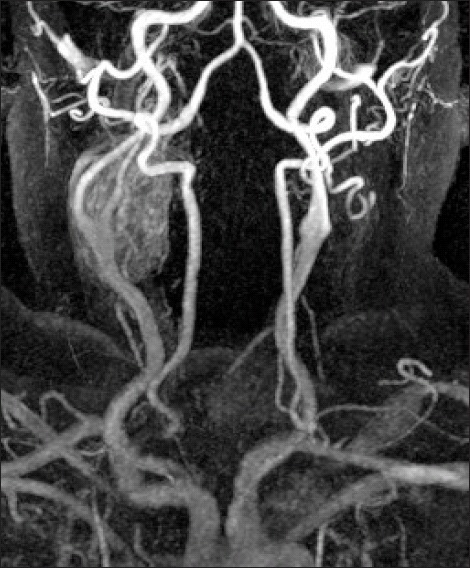

Investigative modalities for the 29 patients included routine ultrasound (n=14), duplex ultrasound (n=5), computed tomography (n=18), magnetic resonance imaging (n=9) (Figure 1), radionuclide perfusion scan (n=6) and percutaneous angiography (n=11). Although percutaneous angiography and radio-isotope scans were commonly performed at the beginning of our series, ultrasound is now advocated as a first-line diagnostic or screening modality. Computed tomography and more recently magnetic resonance imaging are now used during pre-operative planning.

Fig 1.

Magnetic resonance angiogram (MRA) with intravenous gadolinium showing an avidly enhancing 4 x 3.5 x 2.5cm right CBT with multiple small blood vessels within (Note the characteristic splaying of the carotid bifurcation with the external carotid artery bowing over the tumour and the internal carotid artery slightly narrowed in calibre as it passes through)

Non-invasive investigative modalities utilised in the work-up of patients with suspected CBT include duplex ultrasound, computerised tomography angiography and magnetic resonance angiography (MRA) 5, 17. Fine needle aspiration is rarely employed because of the risk of carotid injury or haemorrhage in these highly vascular tumours and open biopsy is clearly contraindicated due to the risk of catastrophic haemorrhage 5. We advocate duplex ultrasound as first line diagnostic or screening modality particular in patients with a positive family history 18. However, similar to other units, we now use MRA to follow-up CBT patients. MRA is safe, non-invasive, highly specific and sensitive for lesions involving the skull base or with a multicentric morphology 19 (Figure 1). Although invasive, routine angiography permits an accurate assessment of vascular anatomy, particularly carotid arterial neo-vascularisation, combined with intra-cerebral flow on the contralateral side, which is important to consider prior to intra-operative occlusion of the ipsilateral carotid circulation when excising the CBT [15].